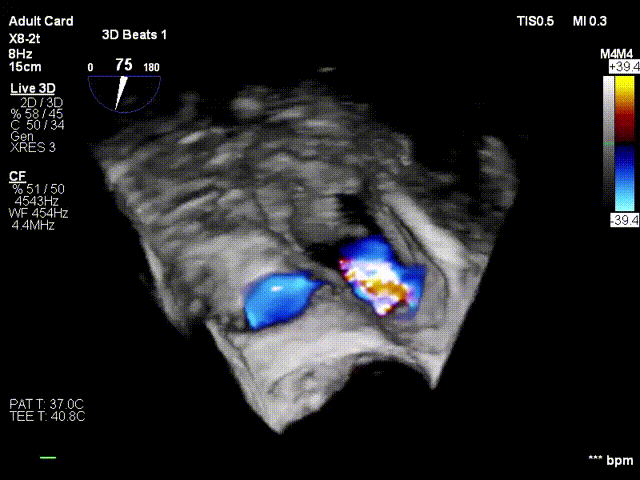

4. The same procedure is performed for the second clip; the clip morphology is stable under ultrasound

Regurgitation assessment: Regurgitation severity reduced from preoperative 5+ to 1+.

Annuloplasty effect: The tricuspid annulus area decreased from 13 cm² preoperatively to 7 cm².